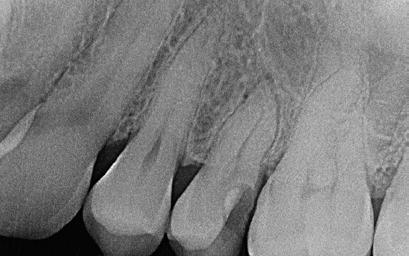

A belső rezorpció miatt kialakult defektusokat, valamint a perforáció következtében kialakult sérüléseket radiológi-

ai felvételek segítségével viszonylag jól el lehet különíteni a külső rezopció okozta ártalmaktól. A belső rezorpciótól szenvedő fogak esetében a radiológiai felvételek excentrikus irányból történő elkészítése során a rezorptív lézió a fog gyökércsatornájával egy irányba mozdul el a felvételen, míg külső rezorpció esetében le fog vetülni a gyökércsatornáról. 1999 márciusában egy 47 éves hölgy páciens arcduzzanattal kereste fel a rendelőnket. Klinikai vizsgálat során a jobb felső nagymetszőfog (11) kopogtatásra való érzékenységét tapasztaltuk. A felső front régióról készült periapikális felvételeken a frontfogakban lévő nagy kiterjedésű III. és IV. osztályú restaurátumokat észleltünk. Az 11-es fog gyökércsúcsa körül periapikális felritkulás volt látható. A 21-es fognál a gyökér középső harmadában belső rezorpciót észleltünk (13. ábra). A páciens kérdésünkre elmondta, hogy a bal felső nagymetszője közel 35 évvel ezelőtt traumás sérülést szenvedett. Mivel abban az időben CBCT-felvételek készítése nem volt számunkra elérhető, így a klinikai adatok alapján azt feltételeztük, hogy a rezorptív lézió bukkális irányba perforálta a gyökércsatorna falát, majd ezt követően az ezt a területet fedő bukkális csontállományt is destruálta.

A frontrégióban végzett szenzibilitás vizsgálat is megerősítette a 11 fogban a fogbélelhalás diagnózisát. Az 11-es fog endodonciai kezelése során a gyökércsatorna biokemo-mechanikai megmunkálását követően a gyökércsatornát meleg vertikális kondenzációs technikával zártuk. A bal felső nagymetsző esetében a gyökércsatorna megmunkálását a rezorpciós üreg koronális határáig végeztük, majd a megmunkált csatornaszakaszt fehér MTA-val töltöttük fel (14. ábra). Amennyiben ennek a fognak a kezelését ma kellene elvégezni, akkor az EndoSequence BC puttyt (Brasseler) használnánk a gyökértömés elkészítésére. Ezenkívül azt is megemlítenénk, hogy manapság egyre gyakrabban próbál-

13. ábra: A periapikális felvételen jól lekövethető a 11-es fog gyökércsúcsa körül látható radiolucens terület körvonala. A 21-es fog gyökerének középső harmadában pedig belső rezorpció jelenlétére utaló jelek észlelhetőek. A rezorptív lézió frontális és laterális irányban is áttörte a csontos falakat, amely következtében a gyökeret körülvevő csontállomány is károsodott. – 14. ábra: A posztoperatív felvételen jól megfigyelhető a 11-es fogba helyezett gyökértömés. A 21-es fog ellátása során a gyökércsatorna megmunkálását csak a rezorptív defektus koronális határáig végeztük. A gyökércsatorna zárására fehér MTA-t alkalmaztunk. – 15. ábra: A 11-es fog gyökércsúcsa körül látható felritkulás teljesen eltűnt. A rezorptív defektus mérete csökkent, valamint a rezorpciós üreg csontosodására utaló jelek is megfigyelhetőek. – 16. ábra: A saggitalis irányú CBCT-metszeten jól látható, hogy a 21-es fogat ép és jól megtartott bukkális kortikális csont fedi. A rezorpciós üreg mérete jelentősen csökkent, valamint az üreg kalcifikálódott anyaggal való telődése is megfigyelhető volt.

koznak a rezorptív léziók injektálható PRF-fel történő kezelésével. Az eddigi eredmények alapján ezzel az eljárással rendkívül kedvező hosszú távú eredményeket lehet elérni. A 21 évvel később készített kontrollfelvételeken látható, hogy az 11-es fog gyökércsúcsánál látható periapikális lézió teljesen eltűnt, valamint a rezorptív lézió mérete is jelentősen csökkent (15–16. ábra)